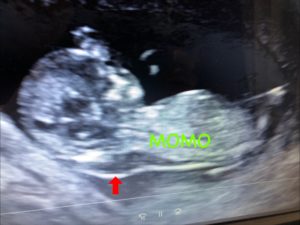

初期超音波検査は、私が妊婦健診で指摘されたNTの厚さの測定をしたり初期に見れる範囲で心臓や各臓器に異常が無いか確認します。

…が、やはり首の後ろの浮腫は素人の私にも明らかでした。

専門医が精密超音波で測定しても5.8mm。

初期超音波検査の結果では染色体異常や先天性奇形の可能性が70%あるという診断でした。

ただ、初期超音波検査での異常はNTのみでその他の奇形や異常所見はありませんでした。